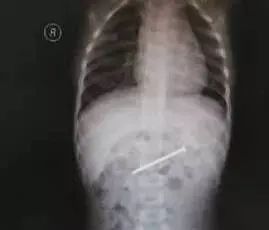

4月20日凌晨,常德市第一人民醫(yī)院接診了一名誤吞鐵釘?shù)?歲患兒童童(化名)。因?yàn)橐幻堕L近4厘米的鐵釘,童童面臨開腹手術(shù)。幸運(yùn)的是,醫(yī)生判斷鐵釘?shù)奈恢煤螅瑳Q定先采取保守治療。通過潤腸及嚴(yán)密觀察,童童成功將鐵釘排出。

配圖來自網(wǎng)絡(luò),與本文無關(guān)。

當(dāng)時情況相當(dāng)緊急,離童童吞下鐵釘已經(jīng)過去一個多小時。鐵釘如果橫插在食管中,極有可能損傷食管黏膜,甚至穿透氣管扎到主動脈弓,造成大出血;若刺破腸管,則會引起穿孔,造成腹膜炎等,嚴(yán)重威脅著孩子的生命安全。當(dāng)班醫(yī)生馬上對童童體內(nèi)的鐵釘進(jìn)行CT定位,發(fā)現(xiàn)鐵釘已經(jīng)到了小腸內(nèi),并與小腸平行。醫(yī)生慎重分析,暫予潤腸保守治療,并嚴(yán)密觀察腹部情況。經(jīng)過醫(yī)護(hù)人員兩天的共同努力,童童順利將鐵釘排出。